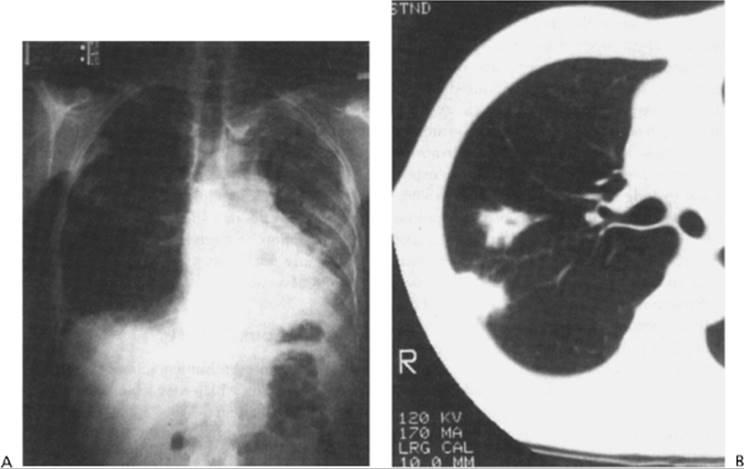

Clinical symptoms of bleomycin pulmonary injury include a nonproductive cough, dyspnea, and occasionally fever and pleuritic pain. Physical examination usually reveals minimal auscultatory evidence of pulmonary alveolar infiltrates, and initial chest films are often negative or may reveal an increase in interstitial markings, especially in the lower lobes, with a predilection for subpleural areas. Chest radiographs, when positive, reveal patchy reticulonodular infiltrates, which in later stages may coalesce to form areas of apparent consolidation. In occasional patients, the initial radiographic changes may be discrete nodules indistinguishable from metastatic tumor; central cavitation of nodules may be present146, 147 (Fig. 15.7). Gallium-67 lung scans or computed tomographic scans (Fig. 15.8) may show the presence of a diffuse lung lesion at a time of minimal abnormality on plain films of the chest; computed tomographic scans are much more sensitive than posteroanterior chest films in revealing the extent of pulmonary fibrosis. Radiologic findings do not differentiate bleomycin lung toxicity from other forms of interstitial lung disease,148 however, particularly Pneumocystis carinii pneumonia. Arterial oxygen desaturation and an abnormal carbon monoxide diffusion capacity are present in symptomatic patients with bleomycin toxicity as well as in patients with other forms of interstitial pulmonary disease. Thus, open lung biopsy is usually required to distinguish between the primary differential diagnostic alternatives, specifically a drug-induced pulmonary lesion, an infectious interstitial pneumonitis, and neoplastic pulmonary infiltration. The findings on histologic examination of human lung after bleomycin treatment closely resemble those previously described in the experimental animal and include necrosis of Type I alveolar cells, an acute inflammatory infiltrate in the alveoli, interstitial and intraalveolar edema, pulmonary hyaline membrane formation, and intraalveolar and, later in the course, interstitial fibrosis. In addition, squamous metaplasia of Type II alveolar lining cells has been described as a characteristic finding.149 In rare cases, a true hypersensitivity pneumonitis may develop, characterized by underlying eosinophilic pulmonary infiltrates and a prompt clinical response to corticosteroids.150

Figure 15.7 A: Typical interstitial pulmonary infiltrates, most obvious in left lung, observed during treatment of a patient with testicular carcinoma. B:Nodular variant of bleomycin pulmonary toxicity in a patient undergoing treatment for testicular cancer. Computed tomographic scan of chest showing a nodular density with central cavitation. On biopsy, the lesion was found to be composed of granulomas with associated interstitial pneumonitis. Appropriate stains and cultures did not reveal infectious agents. (From Talcott JA, Garnick MB, Stomper PC, et al. Cavitary lung nodules associated with combination chemotherapy containing bleomycin. J Urol 1987;138:619.)

Figure 15.8 Computed tomographic scans of the chest before (A) and after (B) treatment for testicular cancer. The multiple metastatic pulmonary nodules partially regressed with therapy, but the posttreatment film shows dense bilateral pulmonary fibrosis as well as a large left pneumothorax and pneumomediastinum. The patient died of bleomycin pulmonary toxicity shortly afterward.